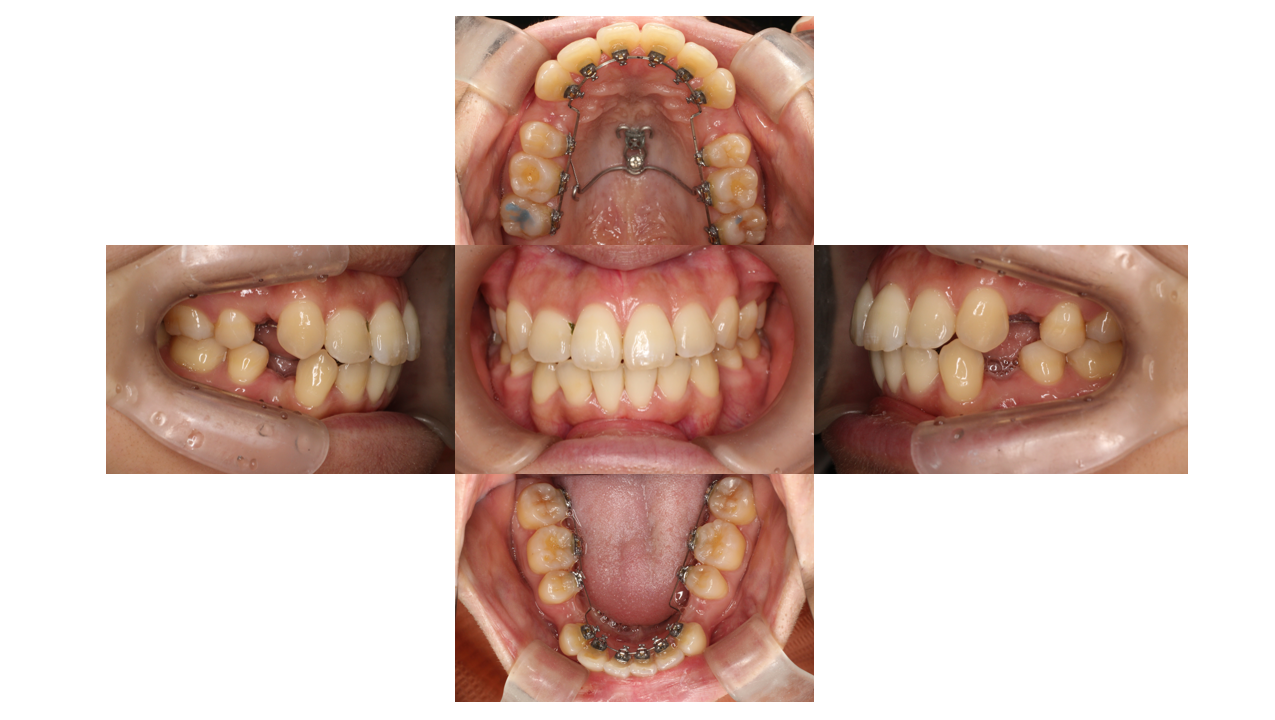

6か月経過

叢生、出っ歯

半年が経過すると初診時気になっていた前歯の凸凹はもう残っていません。

角度のついていた前歯も真っ直ぐになってきています。